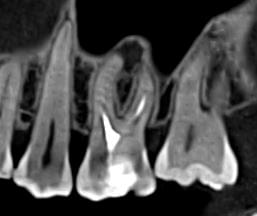

Ми розуміємо, наскільки важлива деталізація в ендодонтії та терапевтичному лікуванні.

Завдяки флагманському обладнанню PLANMECA, ми отримуємо знімки з мінімальним рівнем шумів та

високою роздільною здатністю, що дозволяє чітко візуалізувати морфологію кореневих каналів,

приховані каріозні порожнини та стан періапікальних тканин.